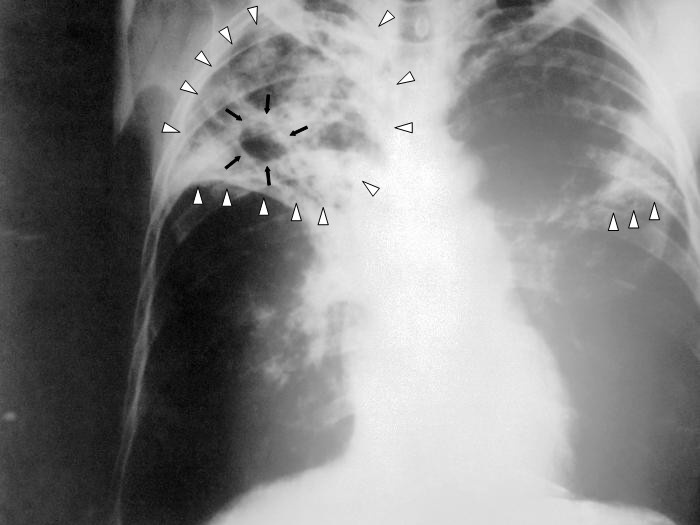

V pardubické firmě Foxconn se objevila tuberkulóza. K dnešnímu dni byly krajské hygienické stanici nahlášeny čtyři případy tohoto onemocnění a to u zahraničních zaměstanců z asijských zemí. Další informace poskytla krajská epidemioložka Ina Valentová.

"Jedná se o cizí státní příslušníky. Pouze ve dvou případech onemocnění má tzv. otevřenou formu. Bylo provedeno epidemické ošetření, jak na pracovišti, tak i v místě bydliště. Dále byly vytipovány osoby, které byly v závažném osobním kontaktu s nemocnými. Tyto osoby se podrobí lékařskému vyšetření a během roku budou mít i lékařský dohled."